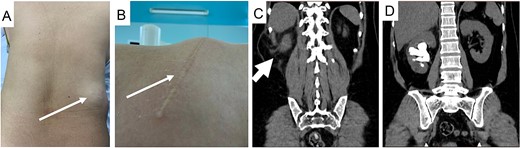

A 74-year-old male presented to our hospital with persistent right flank pain for 5 months who had undergone previous open nephrolithotomy to treat a staghorn stone 10 years ago. He was classified ASA class III due to moderate heart failure, characterized by a 40% ejection fraction. Physical examination revealed a bulky mass on the right lumbar region lateral to the anterior axillary line, consistent with CT scan findings (Fig. 3). A 27 mm stone was observed in the right ureteropelvic junction (UPJ).

Patient’s CT scan shows right UPJ stone (A) and lumbar hernia with mesentery inside (A and B, arrow).